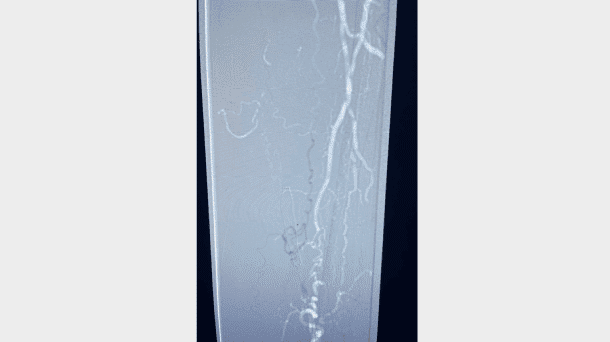

An 83-year-old male with past medical history of diabetes, hypertension, coronary artery disease, a prior bypass, and peripheral artery disease, including right lower extremity chronic limb threatening ischemia (CLTI) with a non-healing right foot ulcer with osteomyelitis lasting greater than 12 months (Figure 1), and a previously treated common femoral artery (CFA) with endarterectomy, returned for right superficial femoral artery (SFA) and tibial chronic total occlusion (CTO) intervention.